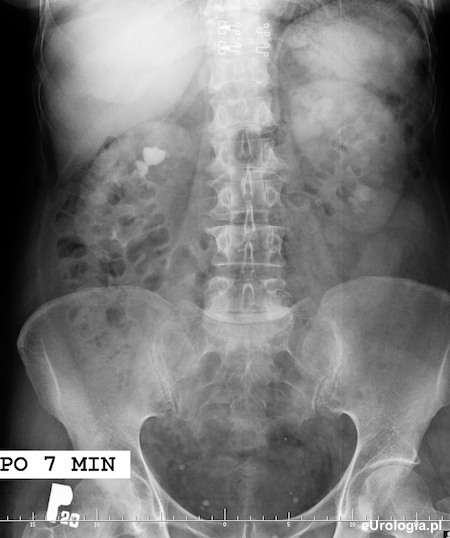

Obustronnie widoczny nefrogram po 7 minutach od podania środka kontrastowego.